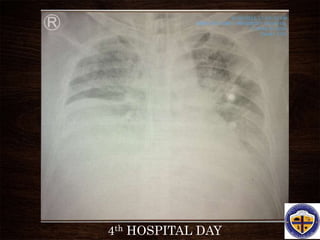

4th HOSPITAL DAY